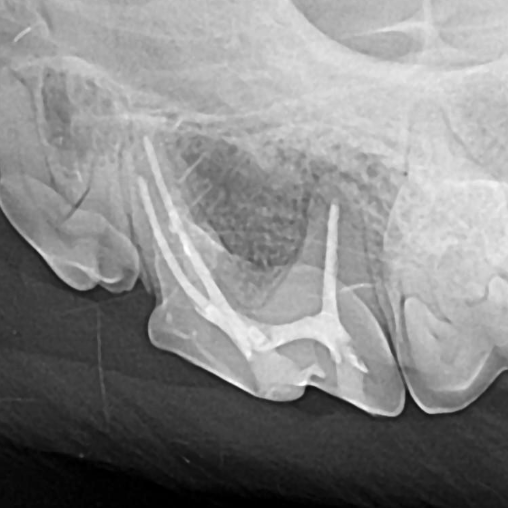

Example of a fractured triple-rooted tooth in a dog:

After: